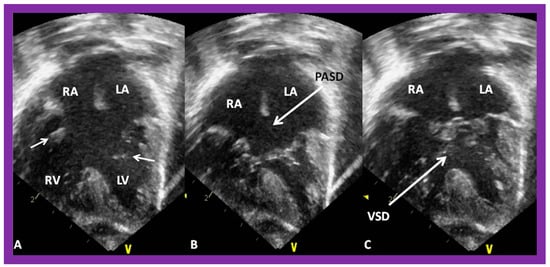

After the visceroatrial situs and the ventricular locations are defined, the relationship between atria and ventricles should be assessed. These relationships are: concordant, with the RA emptying into the RV and the LA emptying into the LV (Figure 30A), and discordant, with the RA emptying into the morphologic LV and the LA emptying into the morphologic RV (Figure 39). Other AV connection abnormalities are: both the right and left atria emptying into a single ventricle (double-inlet left ventricle (Figure 30B)), both atria emptying into both ventricles via one common AV valve in the form of AV septal defect (Figure 42), a common atrium emptying into a single ventricle via a single AV valve (the so-called cor biloculare) (Figure 43), a common atrium emptying into inverted ventricles via a single AV valve (Figure 44) and atresia of either tricuspid or mitral valve (Figure 45). In addition, straddling or overriding of the AV valve over the ventricular septum may also occur. Such abnormalities may be defined by methodical echocardiographic imaging with the rare need for MRI, CT, and angiographic studies.

Figure 42. Echo images in apical four-chamber projections demonstrating the connection of a common atrioventricular valve with the right (RV) and left (LV) ventricles. In (A) (small arrows), the atrioventricular (AV) valve is open, whereas the AV valve is closed in (B,C) during varying phases of the cardiac cycle. Atrial septal defect of ostium primum (PASD) type of large size in (B), as well as a large ventricular septal defect (VSD) in (C), are illustrated. LA, left atrium; LV, left ventricle; RA, right atrium; RV, right ventricle. Replicated from reference [41].